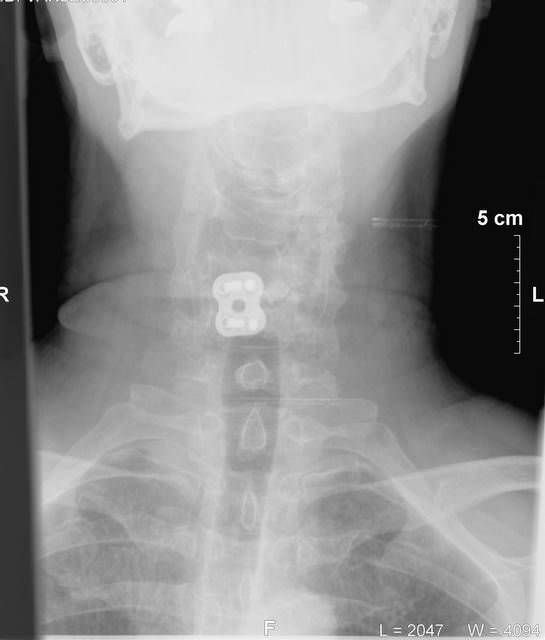

Les Posted September 18, 2010 Report Posted September 18, 2010 caused by decades of affirmative nodding. Click to Enlarge 25.82 KB

Tom Raymond Posted September 18, 2010 Report Posted September 18, 2010 caused by decades of affirmative nodding. Click to Enlarge 25.82 KB Ouch! So just how long have you been married?[:-angel]

gtblum Posted September 18, 2010 Report Posted September 18, 2010 What the hell is that thing? Is it one of those chips they use for finding lost people?